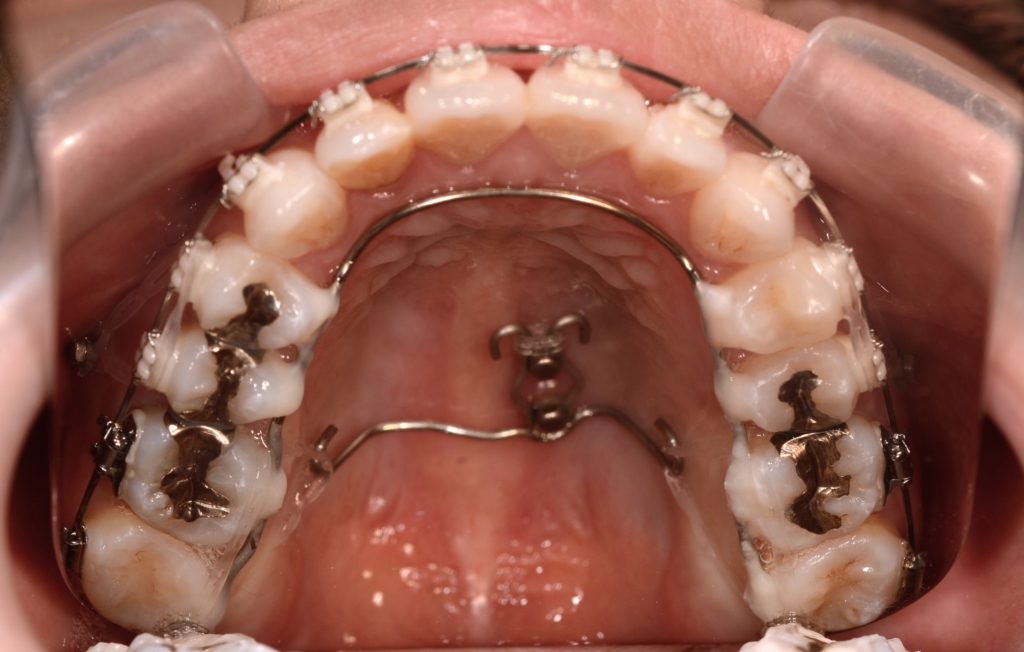

矯正後の状態をレントゲン写真で確認すると、

【保定】 上下ともフィックスタイプ&クリアリテーナー

【治療期間】 約2年10カ月間

【治療費用】 92万6千円

・スタンダードタイプのマルチブラケットシステム

・アンカースクリューを計6本

・PLAS&パラタルバーを使用 【抜歯】

上下の左右の奥歯を1本ずつの計4本(全て第一小臼歯)を抜歯